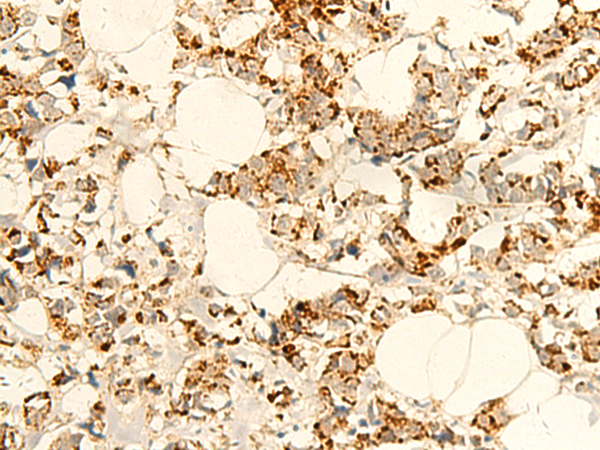

分类: 科研抗体货号: P10113别名: EIF2B; EIF-2Bbeta应用: IHC反应种属: Human, Mouse, Rat